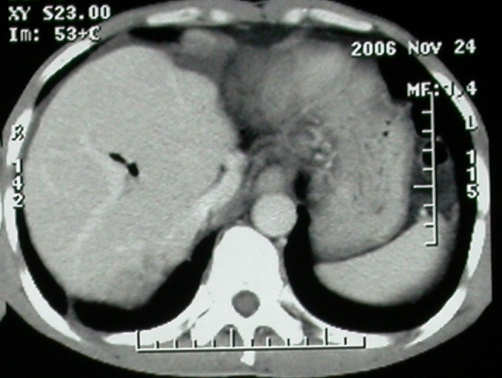

增强ct所见【动脉增强期】

增强ct所见